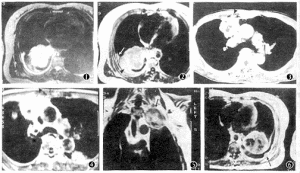

3、超聲心動圖和都卜勒超聲檢查心血管疾病的超聲診斷當今超聲心動圖雖不能直接測量增高的肺動脈壓,但肺動脈壓增高引起的某些間接而特徵性的超聲徵象,對肺動脈高壓的判斷卻頗有幫助。常見的徵象有:

(1)右心室肥厚和擴大:右心室肥厚是慢性收縮期負荷過重的直接後果,不僅與肺動脈高壓的程度和時間有關,也可能與個體對肥厚反應的調節有關。右心室游離壁在輕度肺動脈高壓時已增厚,心室間隔也增厚,運動幅度減弱,或呈同向運動。78%原發性肺動脈高壓患者有右心室增大。正常右心室游離壁厚度≤4mm,右心室內徑小於20mm。

(2)肺動脈內徑增寬和膨脹性下降:二維和M型超聲心動圖可清楚顯示中心肺動脈擴張。正常主肺動脈內徑小於25mm,右肺動脈內徑小於18mm。肺動脈壁順應性隨壓力的增加而下降,收縮期擴張也隨之變小。

(3)三尖瓣和肺動脈瓣反流:心臟增大和瓣環擴張可引起三尖瓣和肺動脈瓣反流。都卜勒超聲心動圖測出的三尖瓣反流率和反流程度與造影所見有良好相關,然而正常人有三尖瓣輕度反流者為0~44%,因此,都卜勒超聲心動圖檢出的輕微三尖瓣反流的意義應結合其他檢查綜合判斷更為穩妥。同樣,正常人肺動脈瓣反流發生率約為13%~90%,檢出輕度反流的意義需全面衡量。肺動脈高壓時反流峰速和時限增加,並隨壓力波動而改變,反流速度與舒張期肺動脈-右心室間壓差相關。

(4)肺動脈瓣運動異常:在肺動脈高壓早期M型超聲心動圖的研究已注意到肺動脈瓣運動的變化,正常情況下舒張晚期肺動脈瓣後葉有一小負向波,稱“a”傾斜,緊接心電圖P波之後發生,反映正常肺動脈舒張末期右心房收縮引起較小的右心室-肺動脈壓差增加,當肺動脈舒張壓輕微增加時可阻止“a”波的出現。

正常“a”波幅度平均為3~5mm,小於2mm可有輕度肺動脈高壓,“a”波消失通常提示肺動脈平均壓大於5.3kPa(40mmHg)。但需注意當右室舒張末壓增加時“a”波可重新出現。肺動脈瓣開放速率增加是肺動脈高壓另一個傳統超聲徵象,它與收縮早期右心室-肺動脈間壓差的大小有關,而與肺動脈壓絕對值無關。M型超聲心動圖肺動脈高壓特徵性所見是收縮期切跡或呈“W”圖型,反映肺動脈瓣收縮期部分關閉,發生率約60%,該徵象有時在無肺動脈高壓存在時也可能出現。